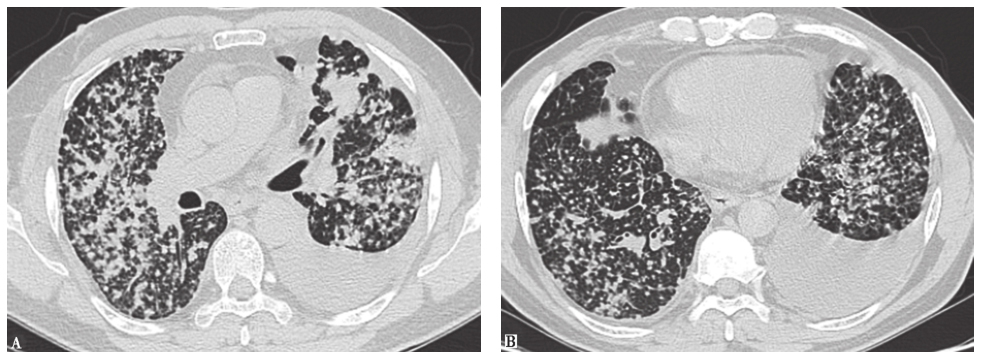

10天前胸部CT见双肺呈随机分布的弥漫性粟粒样小结节影(图2)。

图2 10天前胸部CT表现